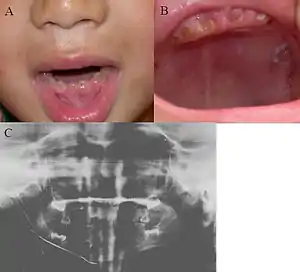

| Oral photographs from an individual with Dentinogenesis imperfecta | |

Dentinogenesis imperfecta (DI) is a genetic disorder of tooth development. This condition is a type of dentin dysplasia that causes teeth to be discolored (most often a blue-gray or yellow-brown color) and translucent giving teeth an opalescent sheen.[1] Although genetic factors are the main contributor for the disease, any environmental or systemic upset that impedes calcification or metabolisation of calcium can also result in anomalous dentine.

Consequently, teeth are also weaker than normal, making them prone to rapid wear, breakage, and loss. These problems can affect both primary (deciduous) teeth and permanent teeth. This condition is inherited in an autosomal dominant pattern, as a result of mutations on chromosome 4q21, in the dentine sialophosphoprotein gene (DSPP).[2] It is one of the most frequently occurring autosomal dominant features in humans.[3] Dentinogenesis imperfecta affects an estimated 1 in 6,000 to 8,000 people.

Clinical appearance is variable with presentation ranging from gray to yellowish brown, but the characteristic feature is the translucent or opalescent hue to the teeth.